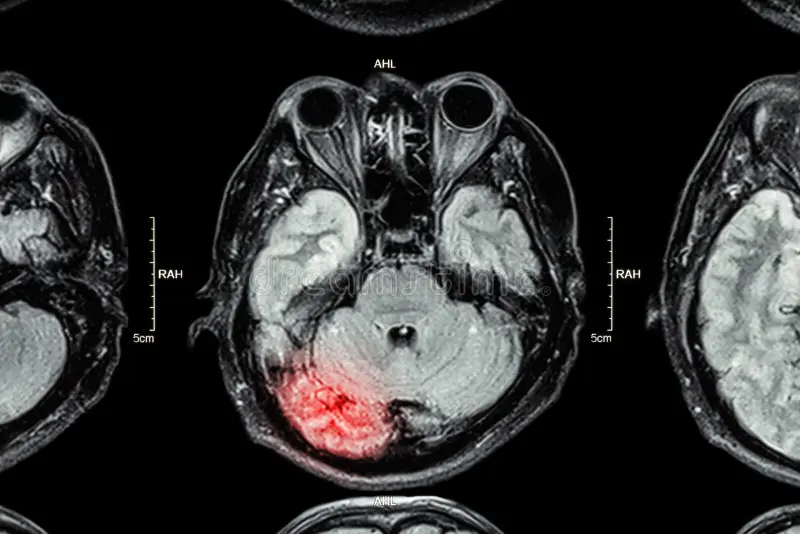

Baxter and Hellewell (2019) focus on repetitive and sometimes subconcussive trauma common in IPV. They emphasize diffuse axonal injury (DAI) – microscopic damage that often does not appear on standard imaging but leads to lasting impairment (p. 663). Survivors showed deficits in attention, memory, and executive function, and women with IPV-related TBI were six times more likely to experience PTSD than other TBI patients (p. 668). Fear of retaliation and clinician neglect further contribute to underdiagnosis (pp. 669 – 670). Although tools such as the HELPS screening instrument show promise, they remain underused without institutional support (p. 670). This research demonstrates how repeated injuries – even when they appear minor – can significantly disrupt daily functioning.

Monahan et al. (2020) identify nonfatal strangulation as one of the strongest predictors of homicide: survivors are over seven times more likely to be killed by partners later (p. 82). Yet up to 40% of fatal strangulations leave no external marks (p. 80). Medically, strangulation can cause hypoxic brain injury and vascular damage (p. 76), while symptoms such as memory loss and vision problems overlap with PTSD (pp. 79 – 80).